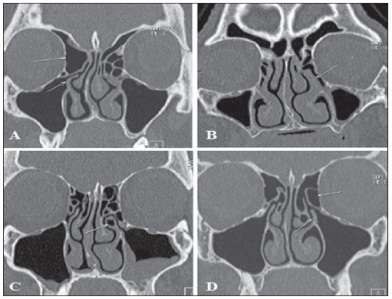

Burun tıkanıklığı yapan nedenlerin tespit etmek gerekir. Burun içindeki bu patolojik durumlarda mutlaka bir kulak burun boğaz hekimi tarafında yapılan endoskopik muayene yapılması çok önemlidir. Hekim gerek görürse ek patolojilerin tespiti için radyolojik inceleme (bilgisayarlı tomografi) yapabilir. Bu titiz yapılan muayenelerde burun tıkanıklığı oluşturabilecek bir kaç unsurunda olabileceği akıldan çıkarılmamalıdır. Burun tıkanıklıklarının en çok görülen nedeni septum deviasyonu yani burun orta bölmesindeki kıkırdak ve kemik sapmalarıdır. Bunun yanı sıra burun içinde yer alan konka adı verilen fonksiyone normal et yapılarının irilikleridir. Ayrıca allerji , sinüzit gibi durmlarda iyi etüd edilmelidir. Bu gibi durumlarda ilaç tedavileri ön plana çıkar. Bazen Allerjik sinüzitlerde polip denilen ekstra et oluşumları, tümörler gibi durumlarda da burun tıkanıklığı olabileceği göz önünde bulundurulmalıdır. Tabiki bu durumlarda cerrahi yöntemlerde farklılık oluşturur.